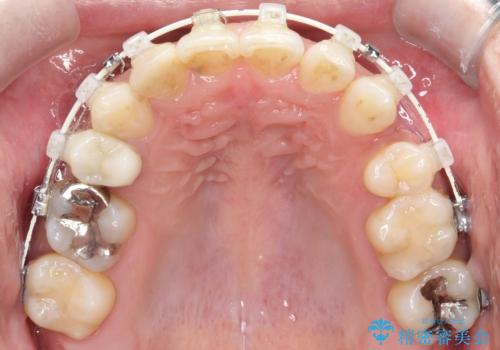

重度の叢生を抜歯矯正で改善|審美ワイヤー矯正+海外出張に伴う中断・再開対応

- 治療計画

重度の叢生により、抜歯を伴う矯正が必要と判断しました。目立ちにくい透明な審美ブラケットを用いたワイヤー矯正を実施しましたが、治療途中での海外出張が決定したため、一度矯正装置を取り外し、保定装置で現状維持を行いました。帰国後に改めて装置を装着し矯正を再開。患者様のライフスタイルに柔軟に対応しながら、最終的には理想的な歯並びと美しい口元を実現しました。